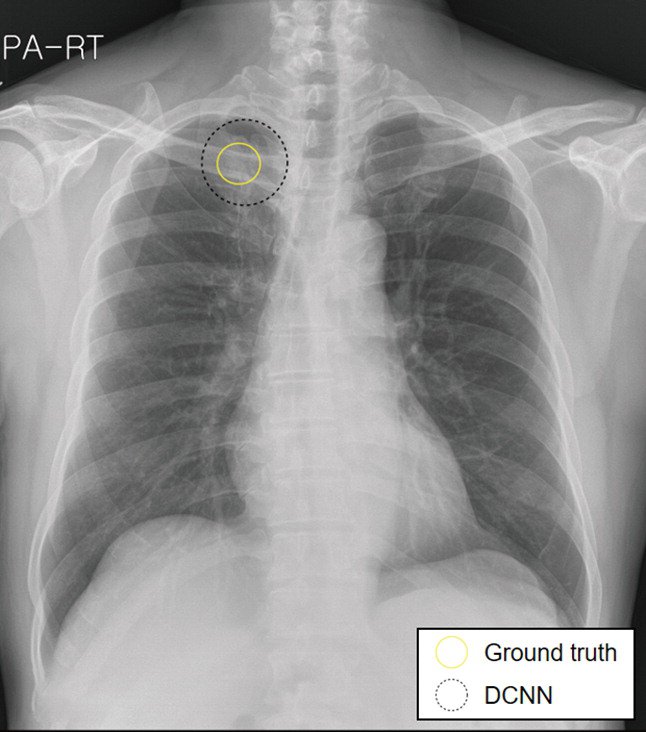

The images in the panels below highlight some of these difficulties. Example 1 shows the chest X-ray of a 62-year-old man with a tumor located in his upper right lung. The tumor is partially obscured by the collar bone and is difficult to see. When analyzed by a group of twelve radiologists, three members of the panel missed the tumor as part of their review. Though they recognized the presence of the tumor during a second review (more detail about that below).

Example 1: 62 year old man with adenocarcinoma

The second image in example 1 (taken from the 2019 Sim paper) highlights how Deep Learning models can help radiologists focus on a region of concern by providing an AI-generated annotation. While three of the twelve radiologist reviewers missed the tumor without the annotation present, all twelve reviewers were able to identify its presence with AI assistance.